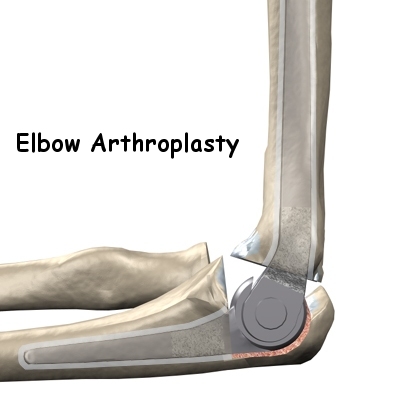

The Artificial Elbow

There is more than one kind of artificial elbow joint (also called a prosthesis). The most common types are like a hinge.

Each prosthesis has two parts. The humeral component replaces the lower end of the humerus in the upper arm. The humeral component has a long stem that anchors it into the hollow center of the humerus. The ulnar component replaces the upper end of the ulna in the lower arm. The ulnar component has a shorter metal stem that anchors it into the hollow center of the ulna.

The hinge between the two components is made of metal and plastic. The plastic part of the hinge is tough and slick. It allows the two pieces of the new joint to glide easily against each other as you move your elbow. The hinge allows the elbow to bend and straighten smoothly.

After the humeral component has been fitted, the surgeon puts together the pieces of the implant and checks to see if the hinge is working correctly. The implant is then removed, and the bone is prepared to cement it in place. The pieces are cemented in place and put together. After another check for proper fit and motion, the surgeon sews up the incision.

Your elbow will probably be placed in a bulky dressing and splint. You will then be awakened and taken to the recovery room.